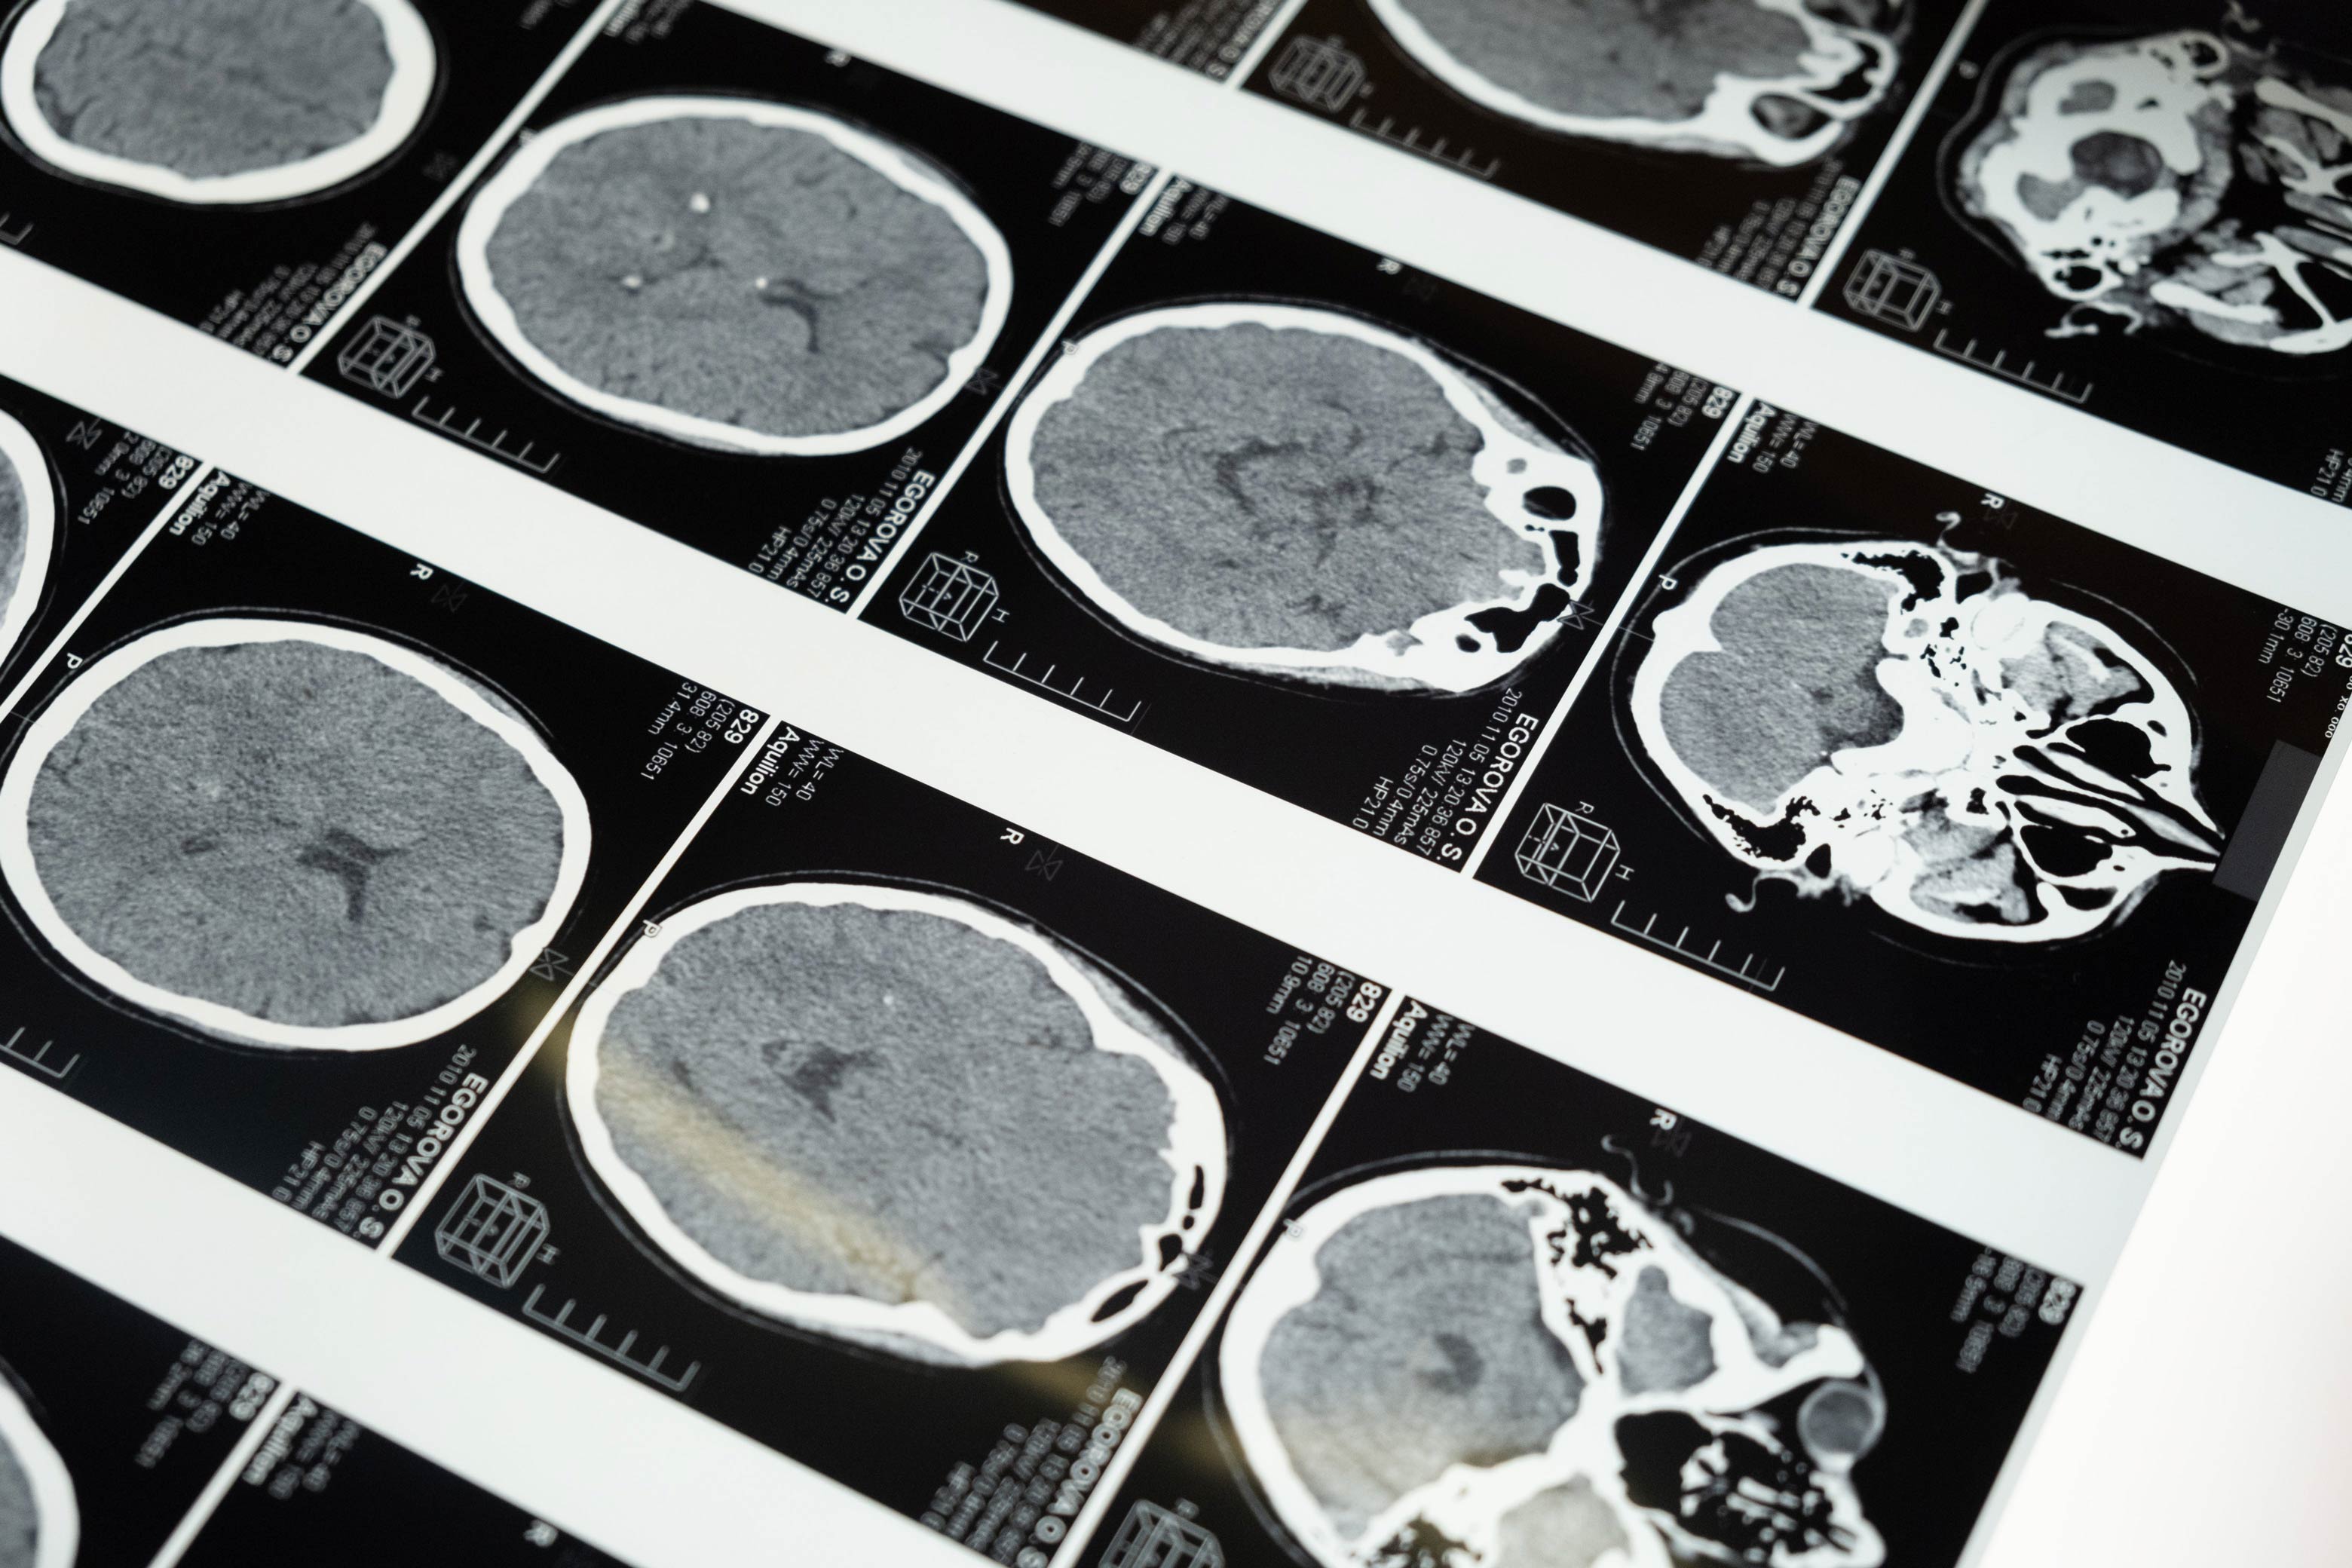

Protege tu cerebro y memoria décadas antes del deterioro. Enfoque preventivo basado en neurobiología del envejecimiento, para optimizar tu funcionamiento cerebral, neuroprotección y bienestar mental.

La investigación en neurociencia muestra que el cerebro adulto puede mejorar, no solo mantenerse. Intervenciones desde los 35 años han mostrado resultados positivos en función cognitiva. Con evaluación y estrategias personalizadas, estudios indican que es posible mejorar áreas cognitivas específicas conforme avanzas en edad, mientras se trabaja preventivamente en factores de riesgo. También, la evidencia científica actual sugiere que el deterioro cognitivo no necesariamente tiene que ser parte del envejecimiento, ya que diversos factores asociados pueden ser modificables mediante atención especializada. La consulta identifica factores que pueden trabajarse ahora para beneficio a largo plazo: